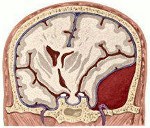

Эпидуральная гематома - травматическое кровоизлияние, располагающееся между внутренней поверхностью костей черепа и твердой мозговой оболочкой и вызывающее местную и общую компрессию головного мозга.

Для эпидуральной гематомы характерно то, что центральная ее часть толще (2-4 см), чем периферические отделы. Представляя собой несжимаемую массу, состоящую из жидкой крови и ее свертков, эпидуральная гематома отдавливает подлежащую твердую мозговую оболочку и вещество мозга, образуя вмятину соответственно своей форме и величине. Характерным и наиболее часто выявляемым источником кровотечения при эпидуральной гематоме являются поврежденные средняя оболочечная артерия и ее ветви, иногда оболочечные вены, синусы и сосуды диплое.